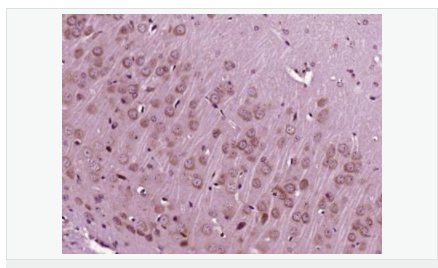

| 產品應用 | WB=1:500-2000 ELISA=1:5000-10000 IP=1:20-100 IHC-P=1:100-500 IHC-F=1:100-500 IF=1:100-500 (石蠟切片需做抗原修復) not yet tested in other applications. optimal dilutions/concentrations should be determined by the end user. |

| 產品介紹 | The protein encoded by this gene is similar to insulin in function and structure and is a member of a family of proteins involved in mediating growth and development. The encoded protein is processed from a precursor, bound by a specific receptor, and secreted. Defects in this gene are a cause of insulin-like growth factor I deficiency. Several transcript variants encoding different isoforms have been found for this gene.[provided by RefSeq, Mar 2009] Function: The insulin-like growth factors, isolated from plasma, are structurally and functionally related to insulin but have a much higher growth-promoting activity. May be a physiological regulator of [1-14C]-2-deoxy-D-glucose (2DG) transport and glycogen synthesis in osteoblasts. Stimulates glucose transport in rat bone-derived osteoblastic (PyMS) cells and is effective at much lower concentrations than insulin, not only regarding glycogen and DNA synthesis but also with regard to enhancing glucose uptake. Subcellular Location: Secreted. DISEASE: Defects in IGF1 are the cause of insulin-like growth factor I deficiency (IGF1 deficiency) [MIM:608747]. IGF1 deficiency is an autosomal recessive disorder characterized by growth retardation, sensorineural deafness and mental retardation. Similarity: Belongs to the insulin family. SWISS: P05019 Gene ID: 3479 Database links: Entrez Gene: 3479 Human Omim: 147440 Human SwissProt: P05019 Human Unigene: 160562 Human Important Note: This product as supplied is intended for research use only, not for use in human, therapeutic or diagnostic applications. 胰島素樣生長因子1(IGF-1)是一種生長調節(jié)激素,由肝分泌并入血液循環(huán)的中性多肽,具有調節(jié)生長和代謝、胰島素樣及促細胞分裂的活性,主要作用于成人。 |